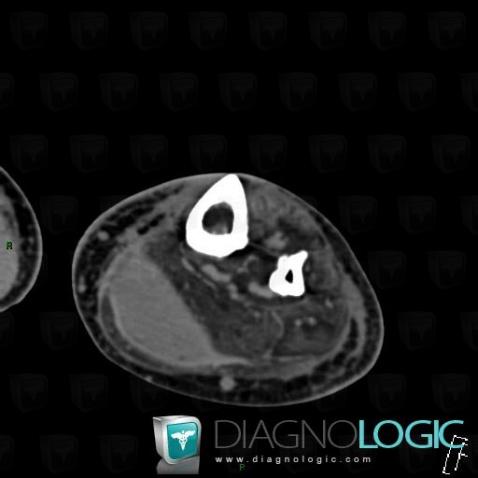

Here is the specific information in the key image above:

- Diagnosis Tennis leg , Location(s) Muscles - Leg, with gamuts

Here is the specific information in the key image above:

- Diagnosis Tennis leg , Location(s) Muscles - Leg, with gamuts